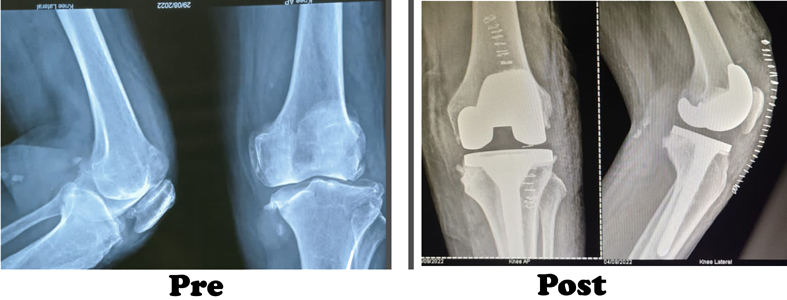

During the knee replacement surgery, the worn out surface (cartilage) of the joint is removed and is capped with implants called as endo-prosthesis. The femur and tibial sides are metal backed and in between there is polyethylene ‘insert’. The patella may or may not be replaced, depending upon the surgeon preference and condition of patellar cartilage.

The surgeon will make an incision on the top of your knee in order to expose the damaged area of your joint. The standard incision size can be as long as 10 inches, but a minimally invasive procedure can result in incisions as short as 6 inches. During the operation, the surgeon moves your kneecap aside and cuts away damaged bone and cartilage, which are then replaced with new metal and plastic components. The components combine to form a synthetic (but biologically compatible) joint that mimics the movement of your natural knee. Most knee replacement procedures take 30min - 1 hour to complete.